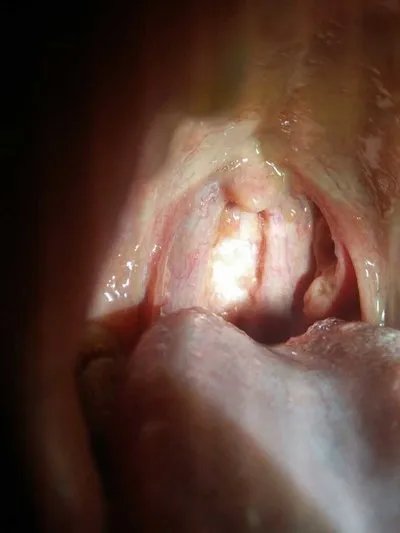

治疗咳嗽的最快方法有哪些?

病因治疗:包括去除诱因(戒烟、停用ACEI制剂、避免接触过敏原等)。轻度咳嗽者无需用镇咳剂。

捶胸、拍背、体位引流可使痰液易排出而减轻咳嗽。咳嗽较重者可酌情选用非成瘾性镇咳剂。成瘾性镇咳药往往仅用于肿瘤、肺梗死、急性左心衰竭引起的咳嗽。

镇咳治疗:首先要确定和处理导致咳嗽的基础疾病。

对没有明确诊断的咳嗽患者不要强力镇咳,也就是说,只有诊断明确的患者,在进行积极有效的对因治疗同时才给予镇咳治疗,短时间应用镇咳药物对控制症状很有帮助,或原发病是不可治愈的疾病时,为了缓解患者症状也可短期应用镇咳剂,通常情况下,不要长期使用镇咳药物来辅助镇咳治疗。